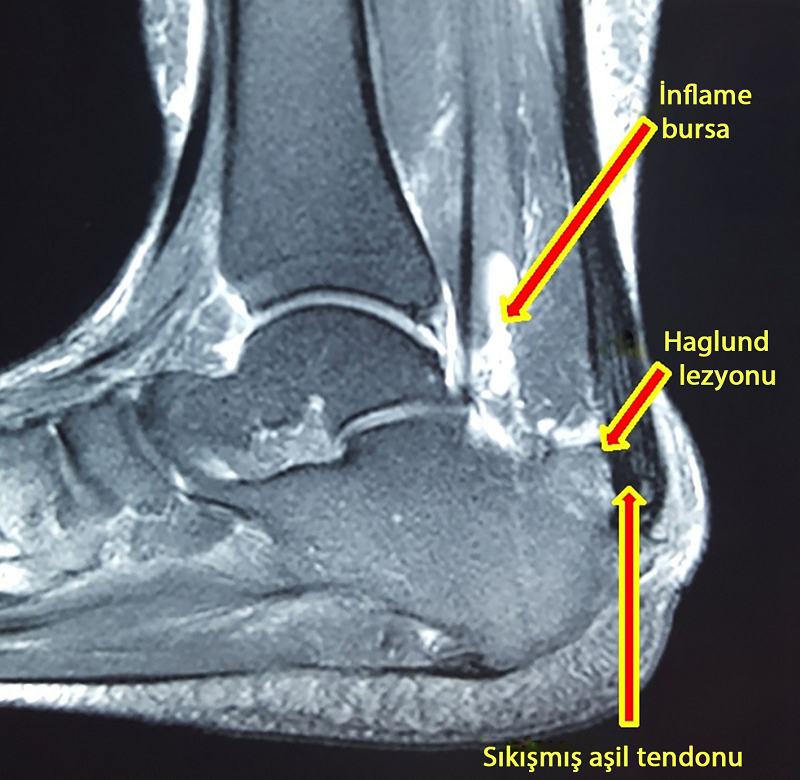

Aynı hastanın MR görüntüsü.